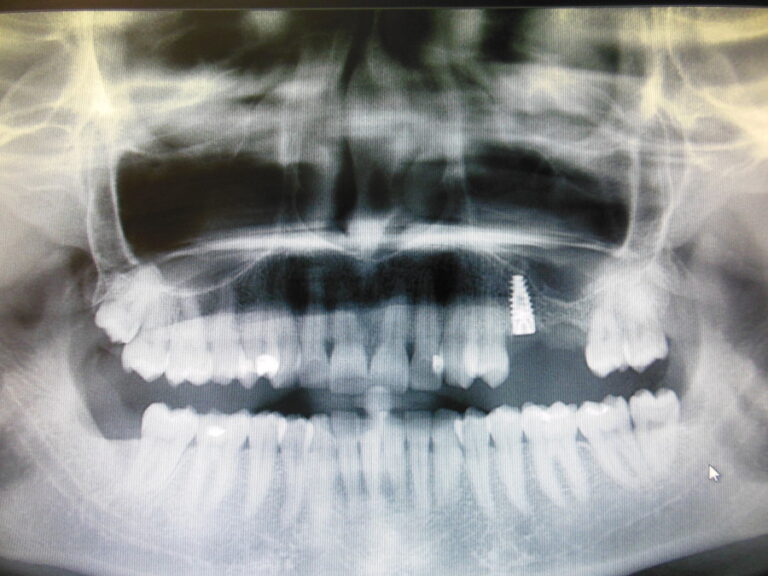

Przykłady implantologii

Zastosowanie implantoprotetyki w przypadku gdy klasyczna protetyka nie sprawdza się.